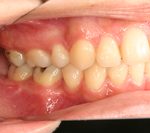

3) 矯正を終えた状態

![]() |

||

叢生(そうせい…歯がデコボコしたり、重なりあって生えていたりする状態)

開咬(かいこう…奥歯はしっかり噛んでいるが、上下の前歯が噛まずに隙間がある状態)